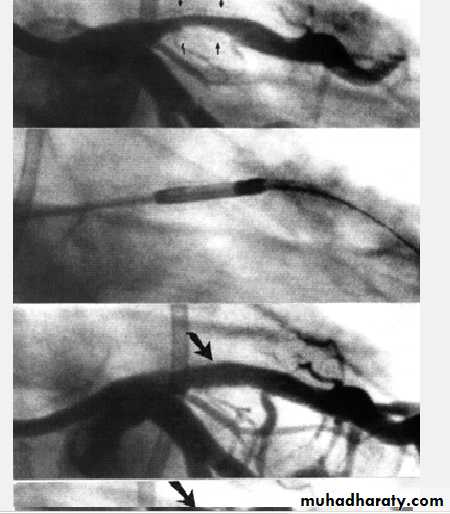

Coronary Angiography

Gold standard to diagnose I.H.D. until now

Demonstrates the anatomy of the artery. By showing

1- severity of stenosis and type of the lesion

a- non-significant stenosis (<70%)

b- Mod or severe (Critical) lesion ( >70% )

2- Extent of the disease:-

single, two ,three vessel disease, Left main

stem disease (> 50%)

3- L.V angiography if done will assess L.V. function

4- If suitable intervention can be done

Indicated for the diagnosis of atypical chest pain

and before revascularization